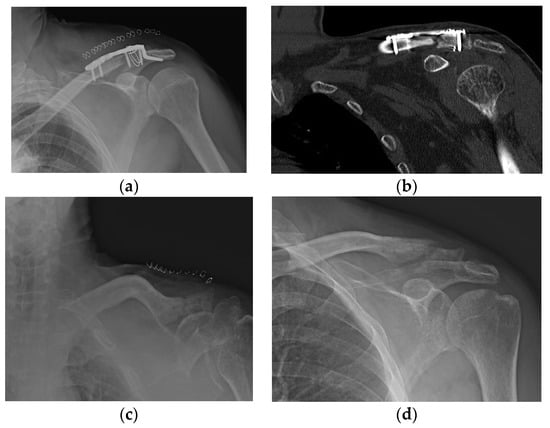

Varying degrees of subacromial erosion occurred in all patients, and acromial fracture occurred in one case in the DCF group and seven cases in the ACD group (Figure 2 and Figure 3). Five (6.7%) cases showed incomplete union and one (1.3%) case showed peri-implant stress fracture in the DCF group (Figure 4 and Figure 5). Four of the five cases of incomplete union showed fracture union without additional surgery during the follow-up period, and one case did not heal at the final follow-up, although the patient did not show any discomfort with non-union (Figure 6). The peri-implant fracture healed with conservative management before plate removal. LOR was observed in nine patients with ACD. Before removing the hook plate, LOR occurred in six patients with ACD. Among these six patients, five showed acromial fracture and one showed serious subacromial erosion (Figure 7). After removing the hook plate, LOR occurred in three patients during the follow-up period. However, none of these patients with LOR among patients with ACD showed tenderness on the acromioclavicular joint or pain during the follow-up period. Regarding acromial fracture, one (1.3%, 1 of 36) case was observed in the DCF group and seven (8.3%, 7 of 33) cases were noted in the ACD group (Figure 4). There was no difference in the incidence of acromial fracture between patients with DCF and ACD (p = 0.066). All eight patients had fracture union without additional surgical treatment during the follow-up period.

Figure 2. Acromial bony erosion. Varying degrees of bony erosions re observed in terms of eroded size and depth, which can be identified after plate removal.

Figure 3. Acromial fracture. (a,b) Acromial fracture may be developed by frictional movement between the hook and the acromion; (c,d) fracture healing is shown without any additional procedure.